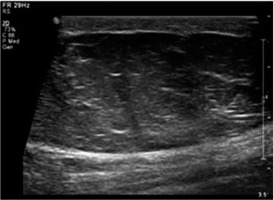

Lipomas, constituting the majority of lesions, were predominantly hyperechoic on conventional ultrasonography, and rest of the lesions were majorly heteroechoic. Doppler assessment was performed to look for the pattern of vascularity and further characteristic parameters, including resistive and pulsatility indices (Figures 1 and 2).

Lipomas constituted the larger part (40%) of the lesions evaluated in this study, and they were quite variable in their appearance, similar to that reported by Fornage et al. [7]. We found that the majority of the lipomas (73%) were hyperechoic (Figure 5). Only two (7.7%) lipomas were hypoechoic, while the rest (19.23%) were heteroechoic. Despite their variable appearance on greyscale images, the sensitivity and specificity for the diagnosis of lipomas utilising an integrated approach stood at 88.89% and 94.74%, respectively. In the systematic review of diagnostic accuracy of ultrasound for soft tissue lipomas by Rahmani et al. the sensitivity and specificity were 86.87% and 95.95%, respectively, concordant with our study [8].

Lipoma – greyscale ultrasound image shows a large, well-defined hyperechoic lesion with few linear echogenic foci within in the subcutaneous plane